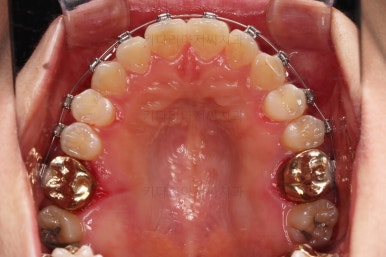

초진 시, 입 안의 모습이에요.

위아랫니가 삐뚤고 교합이 약간 맞지 않네요.

입 안만 보면 심플하게 교정하면 되겠다 싶지만, 문제는 다른 곳에 있었어요.